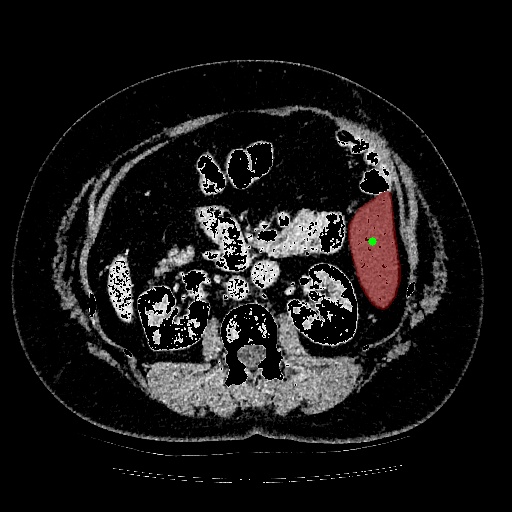

Domain change indicates that the evaluation set is derived from a different modality compared with the train set. We evaluate our model on remote sensing and medical imaging tasks. For remote sensing, we random sample 200 images and corresponding masks from the mapping challenge and denote it as the Remote-200 dataset. For medical imaging, we random sample 500 images and corresponding masks from Liver Tumor Segmentation Challenge and denote it as LiTS-500.

| Image | GT Mask | RITM IoU=18.76% | RAIS IoU=51.99% |

![]() |

| Image | GT Mask | RITM IoU=2.85% | RAIS IoU=84.50% |

In this experiment, we train our model on COCO+LVIS [16, 7] and evaluate the performance on Remote-200 and LiTS-500, respectively. In this case, the data domains are completely different between training and testing.

Table 2 shows the adaptation performance of different methods on the two datasets, where ADM denotes whether the model uses the ADM part or not, and Optim denotes whether the model uses the optimization strategy. Note that, if the model does not use either ADM or Optim, it can be regarded as the off-the-shelf method, e.g. RITM. If the model uses Optim, it can be regarded as previous on-the-fly methods. As we can see, our RAIS models with both proposed ADM and Optim show the best performance compared to other methods, which means our method is more robust to domain changes. An interesting observation is that the performance deteriorates with only the ADM part. It means that although the learning ability of the model is becoming stronger with extra components, the adaptability would not get better with it. Thus, A specific adaptation module with a well-designed optimization strategy is necessary for the interactive segmentation model. Furthermore, we show the samples of visual comparison on Remote-200 and LiTS-500 in Figure 4. As we can see, the test images in remote sensing and medical images are much different from the training set, i.e. COO + LVIS. The previous method cannot handle the image annotation with the domain changes, while our method with the well-designed adaptation module and optimization strategy shows the much better results.